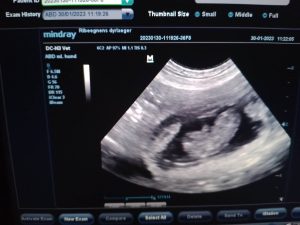

Kurz vor der Geburt war Sie wieder zu einer kontrolle, und hier sagten die TA das es 10 Welpen währen.